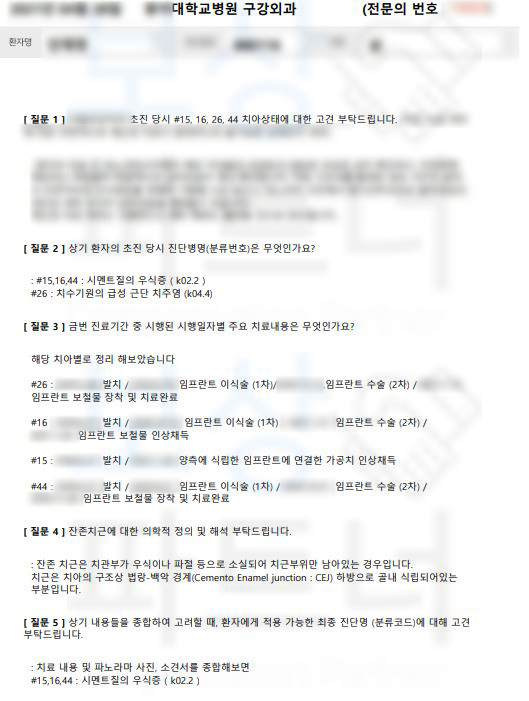

공신력있는 제3병원의 전문의의

소견을 의뢰하였습니다.

의뢰인의 치아에 대해 K02.2 시멘트질의 우식증 K04.4 치수기원의 급성 근단 치주염 적용이라는 증거를 수집했고 약 2달간의 분쟁이 오간 결과 발치후 임플란트 보험금 인정 받을 수 있었습니다.